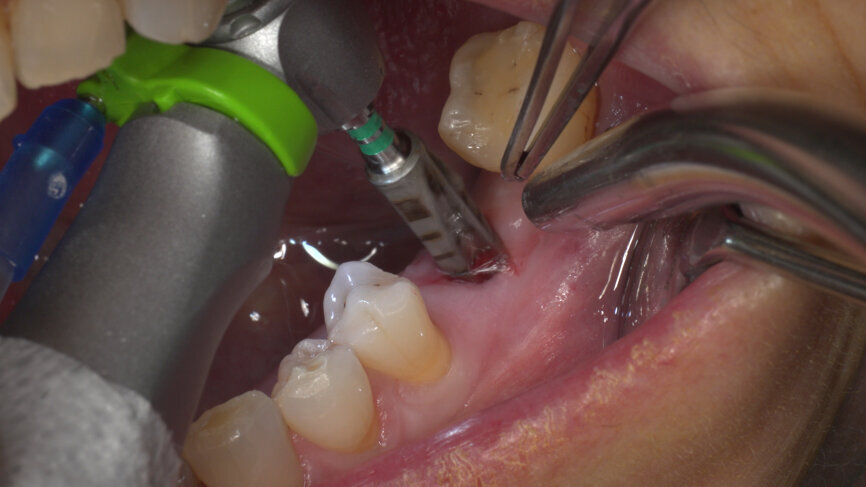

Under local anaesthesia, a flapless implant surgery technique was performed in position #36. Owing to the quality of the bone, staged drilling with continuous saline irrigation was performed in order to obtain a proper, safe insertion torque (Figs. 2–7). One implant (BLT, Regular Neck, Roxolid, ⌀ 4.8 × 10.0 mm) was placed, and a torque of 42 N cm was applied (Figs. 8–11).